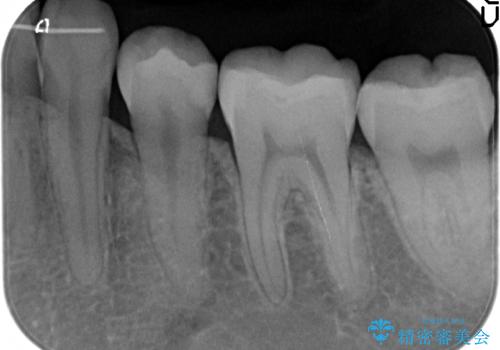

- 奥歯の歯と歯の間が虫歯になっていました。

セラミックインレーで治療しました。

- 14万円 左下56:セラミックインレー7万円×2本費用は治療当時の料金となります

虫歯が進行して、神経に近くなると、冷たいものが染みたりする神経症状が出てきます。

そういった自覚症状が出る前に処置することをおすすめします。